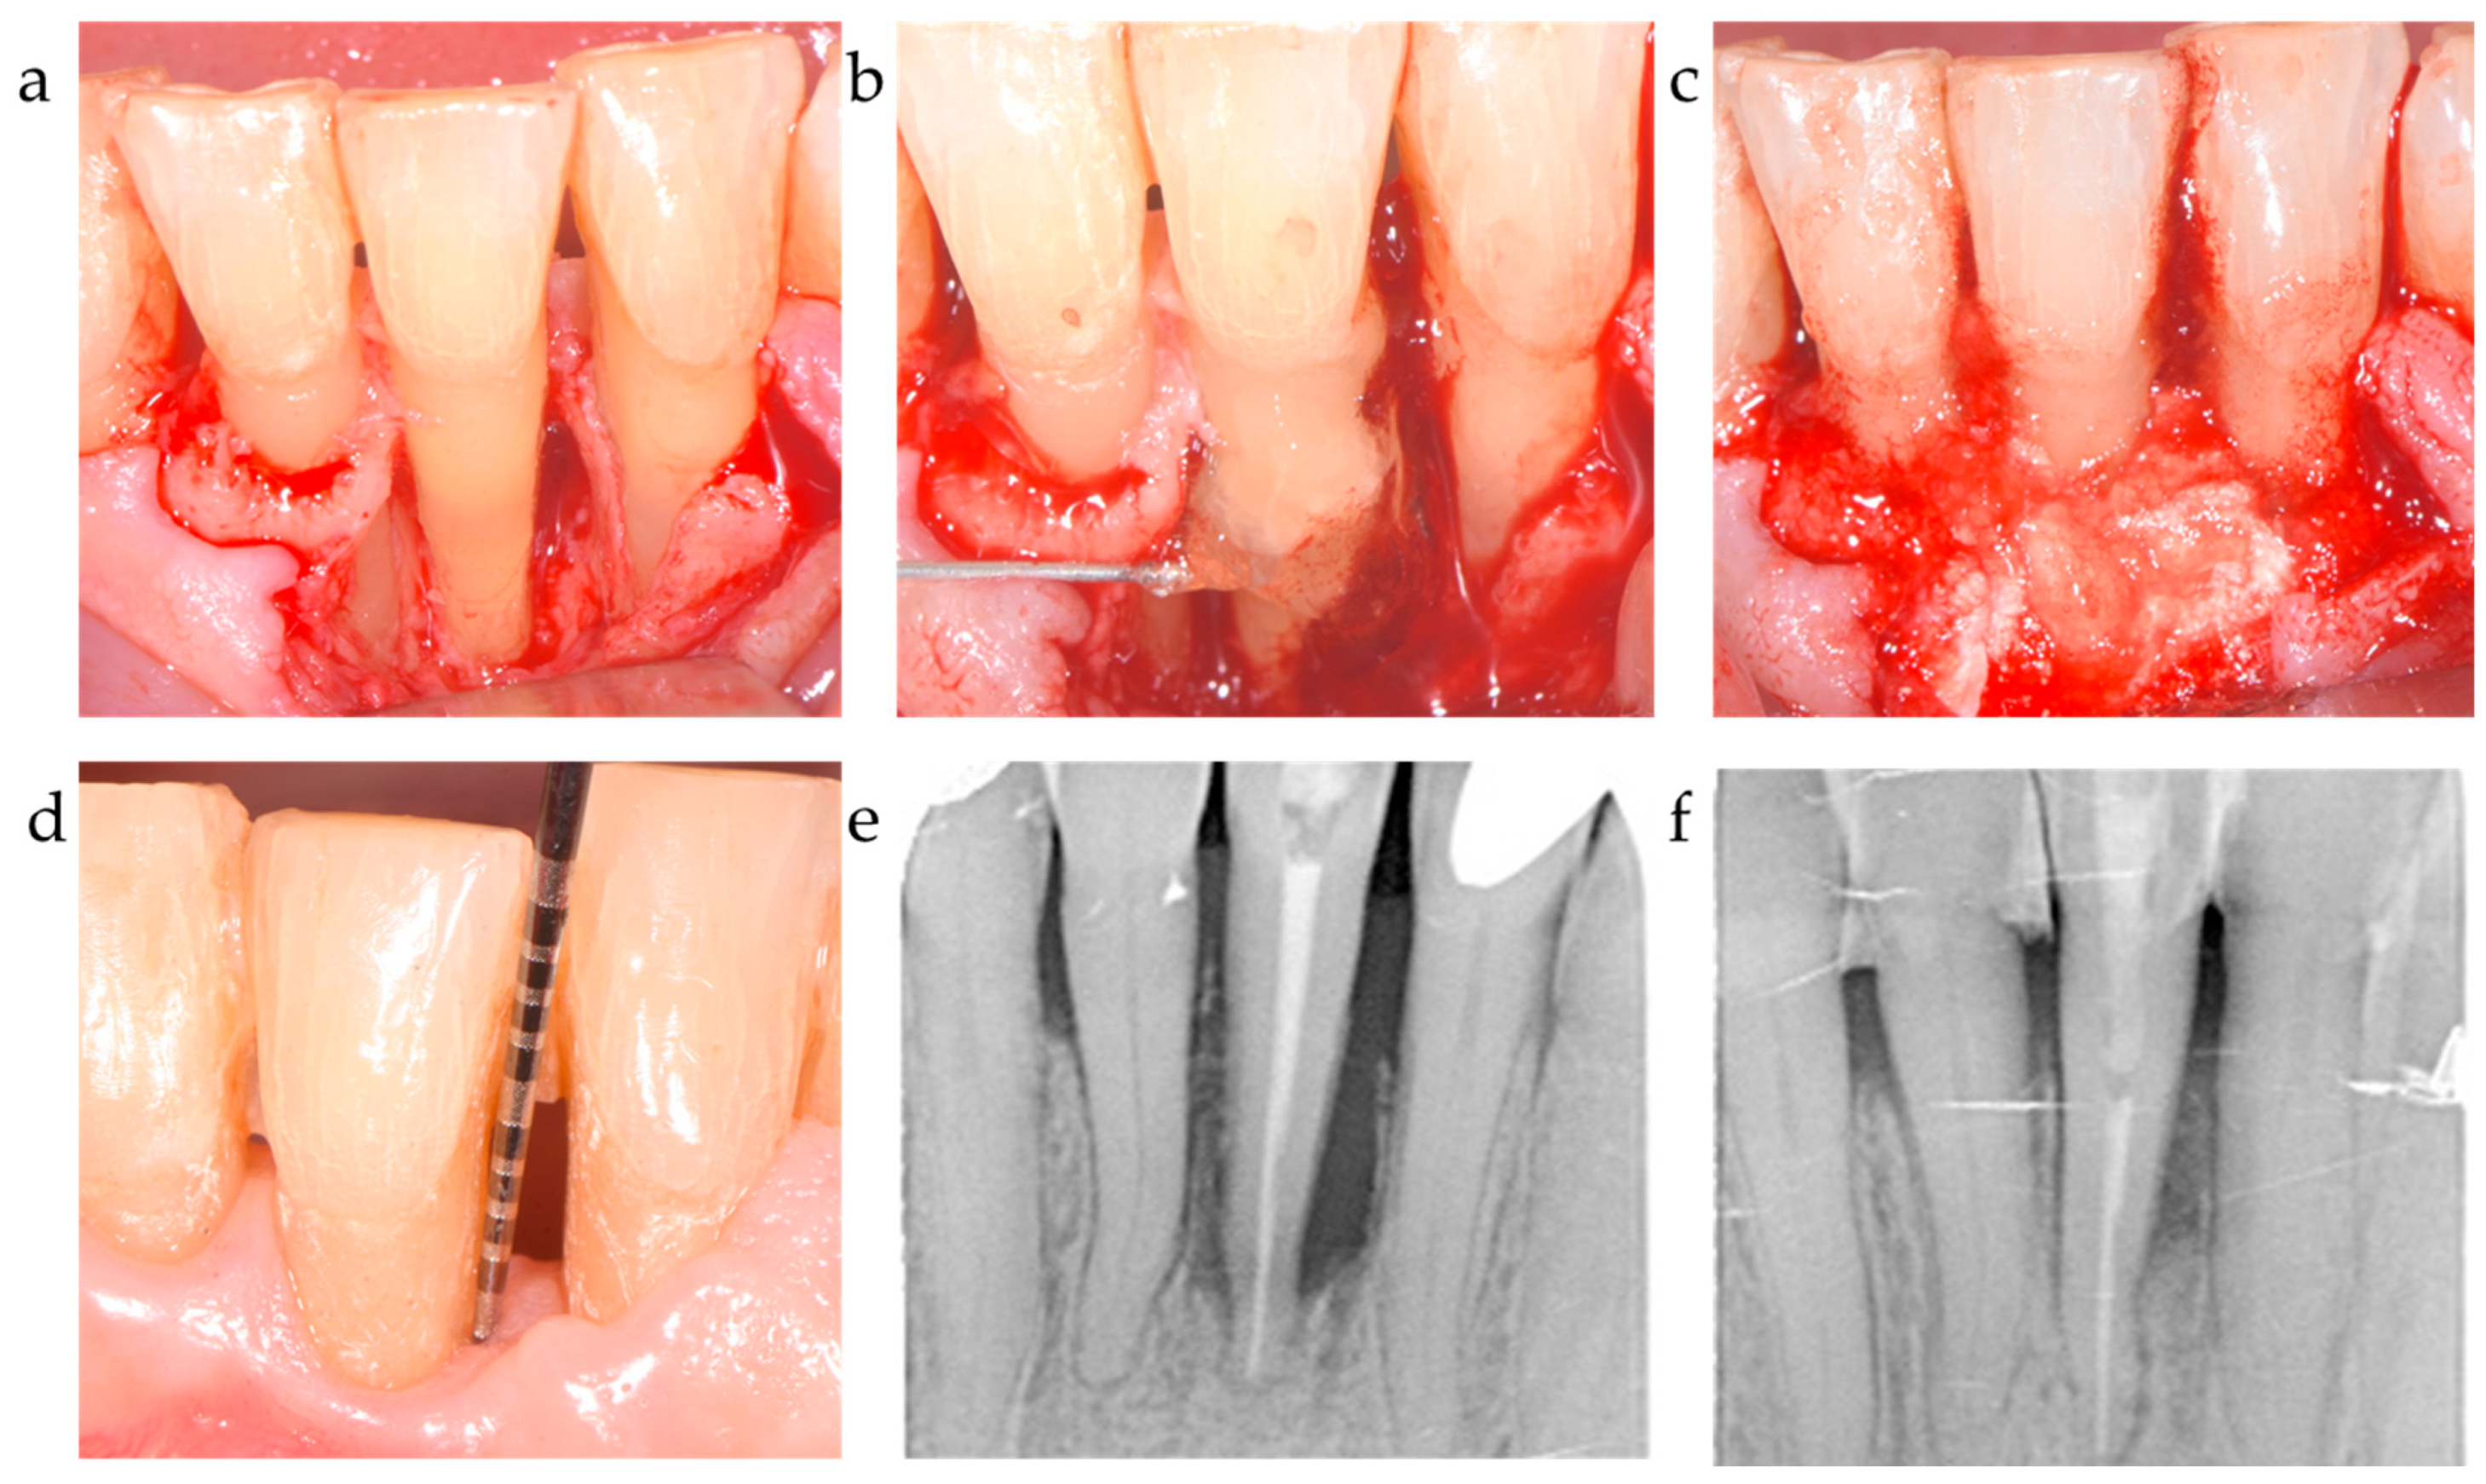

Figure 2.

Center 1 showcase: (a,b) radiographically observed change in bone level around tooth 31 before surgery and 12 months post-op; (c,d) defect extension and defect grafting at surgery; (e,f) the result of grafting.